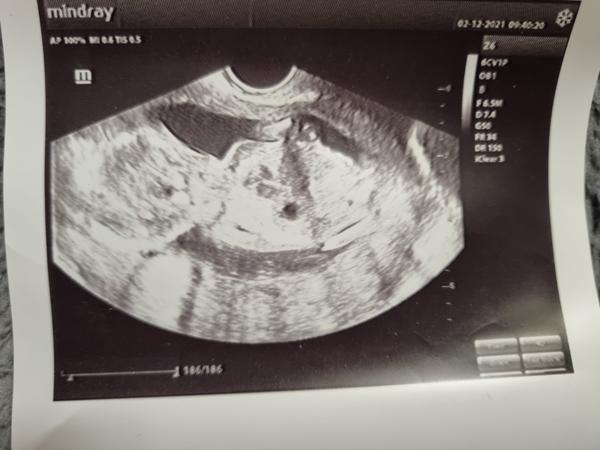

Pohlavie dieťaťka v 14. týždni

Dnes som bola na sone som 14 tt, doktor mi powedal, ze to bude asi chlapec ale nieje si istý na 100%...je tam sanca, ze by to bolo diewcatko? ☹ , nie ze by som chlapca nechcela, ale som buduca slobodná mamička, tak som tuzila po diewcatku,newiem no, ale widim too na mnohych chlapcoch, ktoorý wyrastali iba s mamami, im wiac chyba ten otec a ten muzsky wzor, ako pri ddiewcatku.. ☹ ☹ ☹

@karin1234 Mne powedal doky, ze to moze byt ajj pupocna snura, newidno to skoro wobec, lebo ked som sa ho pytala ci si to mysli na 100%, powedal ze urcite nie, no nic uwidim este, bude to lepsie widno w 17 tt ? lebo idem na odber krwi tak mi rowno urobí aj sono....